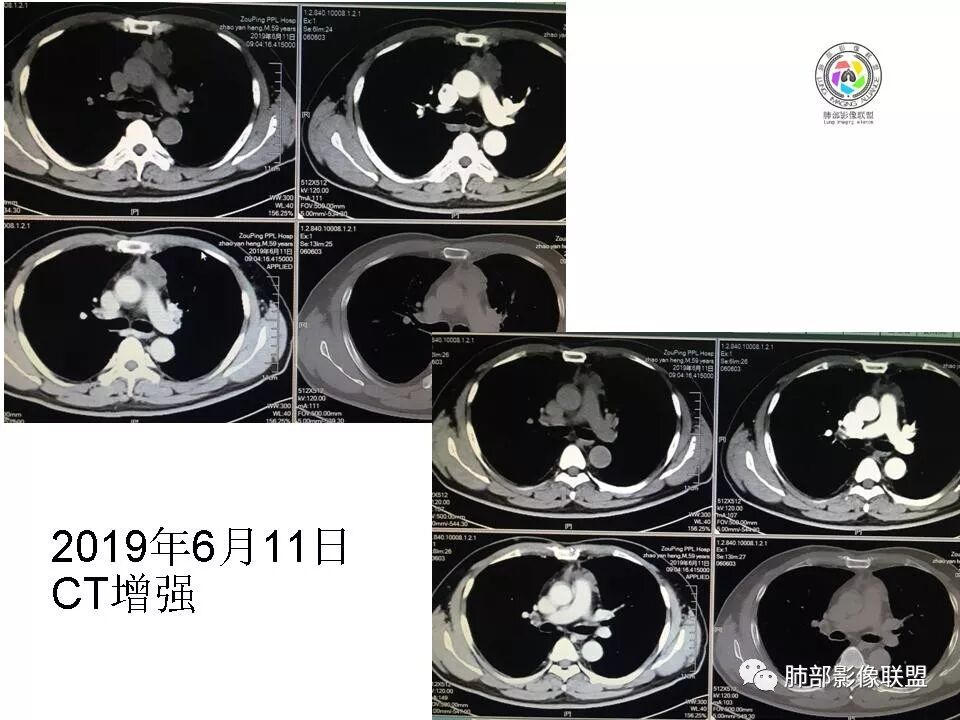

【每日晨读】胸腺瘤or胸腺癌,且听南边老师娓娓道来

8.29晨读病例

男,59

2015年小,2019年增强,不规则强化不均匀。

48-60-70,28-30-24,不规则渐进性强化,密度不均。

诊断:侵袭性胸腺瘤